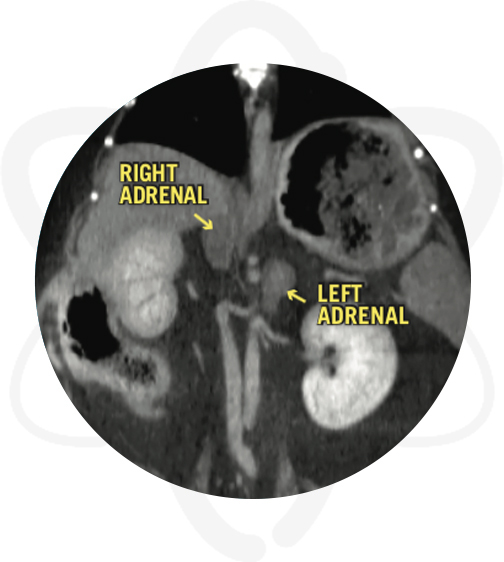

Patient is a 7 yr old, MN, Yorkie with diagnosed with hyperadrenocorticism. A CT scan of the abdomen and pituitary gland was requested to differentiate pituitary vs adrenal dependent hyperadrenocorticism.

- Bilateral symmetrical enlargement of adrenal glands

- CT Scan is consistent with pituitary dependent hyperadrenocorticism